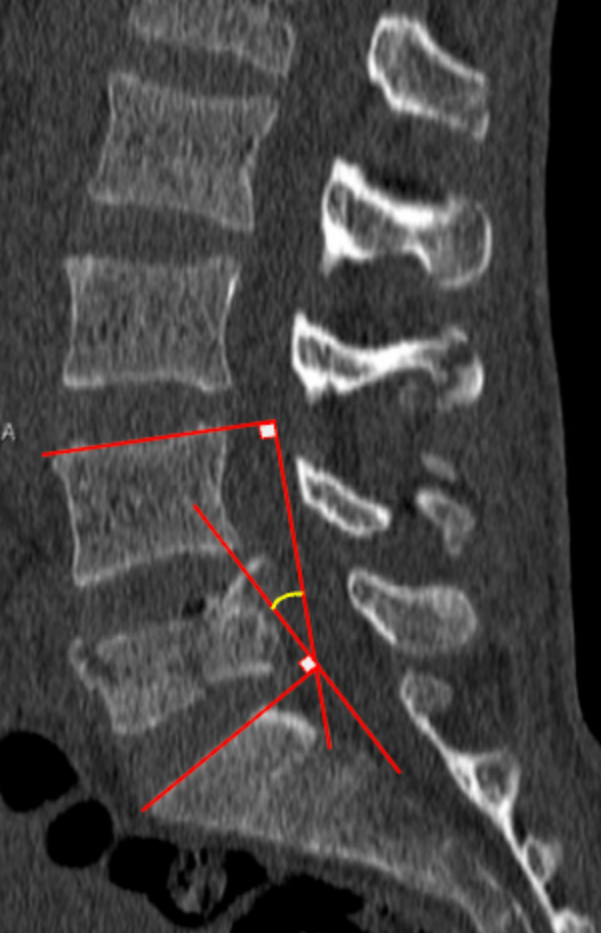

Kyphotic Angle